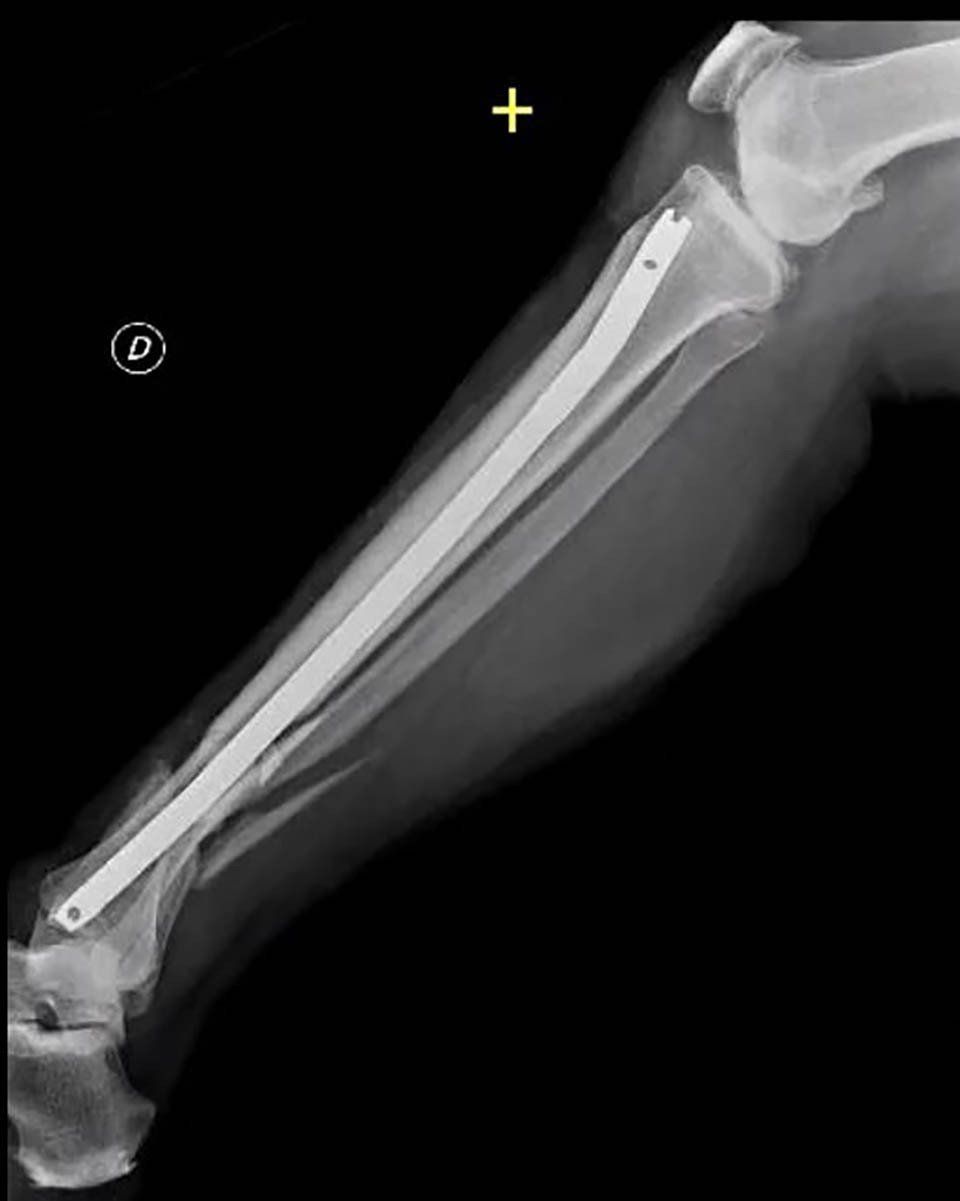

All non-surgical or surgical treatments for bone repair follow a basic rule: the fractured bone segment must be realigned, and the movement of the two fragments must be limited until complete healing. Some fractures, especially if complex, can be held in place with casts or splints; others require more stable surgical fixation, which can be achieved with intramedullary nails, plates, screws, or external fixators.

- Internal fixation: Orthopaedic surgeons use intramedullary nails, metal plates, and screws to stabilise pseudoarthrosis. Often, bone grafts are used to assist stability and promote healing.

- External fixation: Orthopaedic surgeons apply an external device to the affected limb using steel wires and pins. This method is preferred for pseudoarthrosis without sufficient stability, infected cases, or those with bone loss.